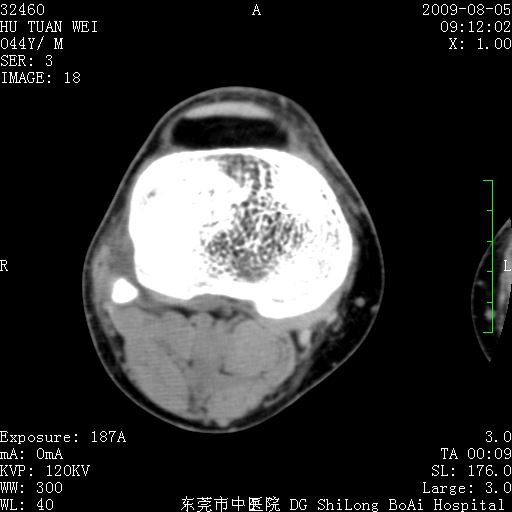

中年男性,膝韧带损伤术前检查!其他病史不清粗,不是我接手病人、且出院了!

1、股骨下段囊状膨胀性病变,边缘硬化明显,内多个残留骨棘呈多房型改变,囊腔密度较高无钙化,膝关节滑膜囊增厚,密度增高,关节腔少量积液。考虑:邻关节囊肿、退变性囊肿(软骨下囊肿)、着色性绒毛结节性滑膜炎、abc、骨巨、良性纤维组织细胞瘤等鉴。虽然年龄偏大,部位于骨端,但有外伤史,本人还是倾向于动脉瘤样骨囊肿(abc)可能性大。邻关节囊肿及软骨下囊肿次之考虑。

2、胫骨髁间棘撕脱骨折,交叉韧带损伤可能;

3、关节退行性改变。

病理结果:色素沉着绒毛结节性滑膜炎

感谢反馈病理结果!本病为慢性关节病变。以关节滑膜高度增生、绒毛结节形成伴含铁血黄素趁着为特点。病因:有炎症、肿瘤、外伤关节出血、代谢障碍、变态反应及感染等学说。增强扫描呈关节腔内单个或多个强化的软组织结节影或滑膜不规则增厚伴关节积液为本病的特征性表现。